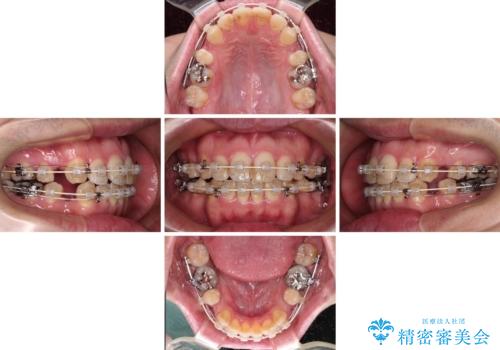

- 審美装置

- 2年6ヶ月

- 30回以上

舌突出癖の改善トレーニングは、仕上がり、治療期間、そして治療後の後戻りに大きな影響を及ぼします。